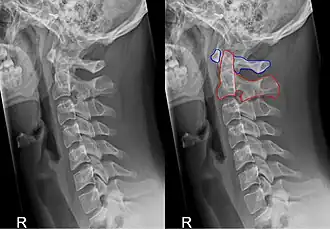

Het is de draaier van de wervelkolom. De axis maakt met zijn tand (dens axis) gewricht met de eerste (C1) halswervel of atlas. Dit is in zijn geheel de articulatio atlantoaxialis. Op de voor- en achterzijde van de dens axis bevindt zich een gewrichtsvlak: de facies articularis anterior die articuleert met de fovea dentis van de atlas, en de facies articularis posterior waartegen het ligamentum transversum atlantis komt te liggen dat de dens op zijn plaats houdt. Atlas en hoofd draaien om de dens axis, een beweging die overeenkomt met het nee-schudden. Verder heeft de atlas dezelfde kenmerken als de andere halswervels.